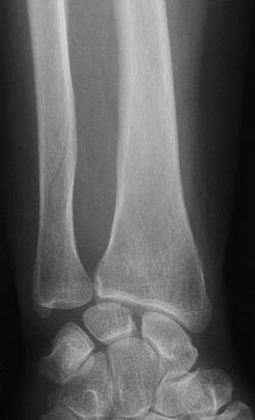

Какой вид перелома большеберцовой кости вы видите// Косой// Винтообразный// Прямой// Компрессионный// +Полифокальный